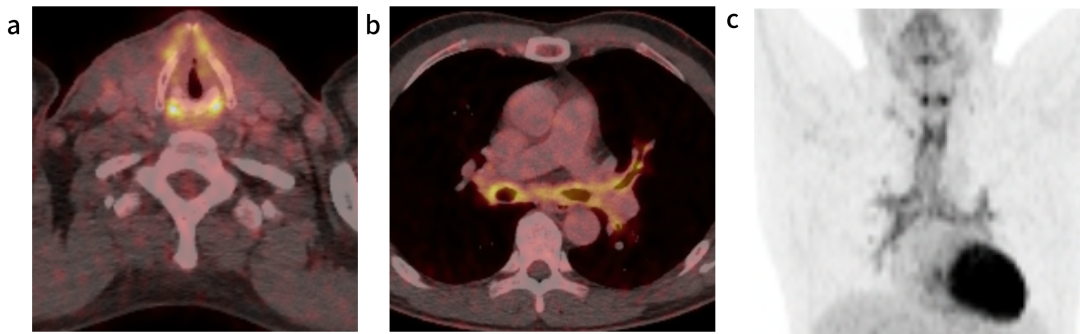

本例患者因临床疑诊RP转诊至风湿免疫科。虽曾考虑行组织活检以明确诊断,但因顾虑气道操作风险而未施行。治疗方案始于大剂量泼尼松龙诱导缓解,后续序贯生物制剂治疗。通过随访核磁共振成像(MRI)评估治疗反应,可见气管支气管壁增厚程度较前部分好转(图3、图4),提示治疗应答。尽管如此,患者仍反复出现呼吸道症状急性加重,说明本病具有易复发、难控制的临床特点。

4. 治疗六个月后的轴向T1加权MRI(T1 FSE)与图3处于同一水平,显示炎症变化部分消退